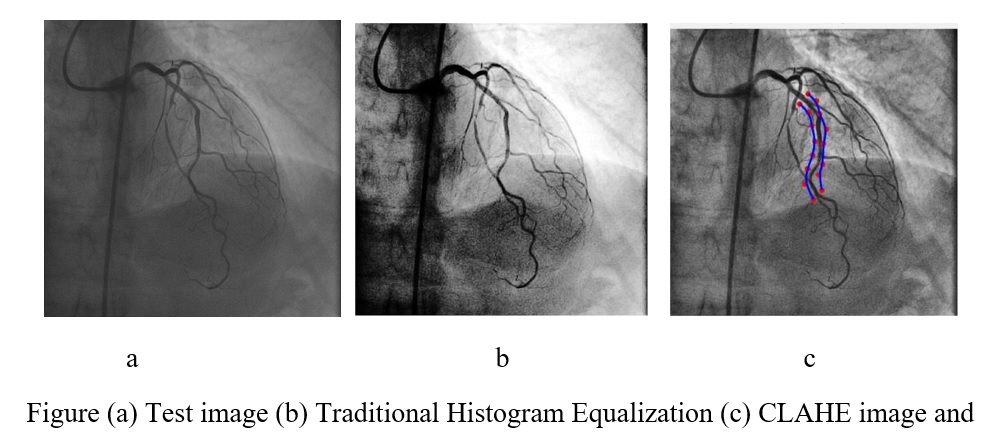

Since images obtained from X-ray angiography generally suffer from poor and variable contrast problem (as shown in Figure 4.2), CLAHE is a good and popular remedy for contrast enhancement compared to standard histogram equalization method.

Advantage of CLAHE over usual adaptive histogram equalization (AHE) method is that it does not over amplify the noise as AHE does.